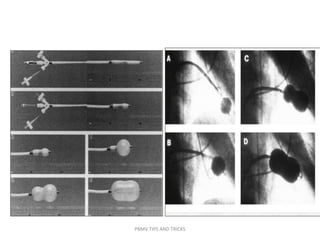

Mansfield balloon

PBMV TIPS AND TRICKS

• An adaptation of the double-balloon technique uses a

monorail approach to deliver two balloons across the

mitral valve over a single guidewire .

• The first valvuloplasty balloon with a short monorail

segment is passed over the wire across the MV, followed

by a second conventional balloon that is then passed over

the wire until it is parallel with the first balloon.

• There are no substantial differences in the mechanism of

delivery of force by two balloons using this approach

compared with conventional double-wire, double-balloon

technique